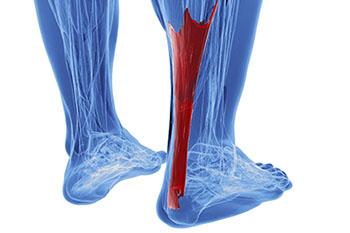

The Achilles tendon is not only the strongest, but also the largest tendon in the human body. The main function of the Achilles tendon is to transmit power from the calf muscles to the heel and the foot.

It’s because of the Achilles tendon that we are able to stand on our toes when walking, running, or jumping. Even with all of its strength, the Achilles tendon can be exposed to injury. Due to its limited blood supply and the high tensions placed on it, the Achilles heel can be left vulnerable if harmed.

Possible conditions that may arise due to injury of the Achilles tendon include tears, ruptures, tendinitis, peritendinitis, tendinosis, tendinopathy, and bursitis. When trying to diagnose if one has issues with their Achilles tendon, a podiatrist will commonly check for any pain, swelling, or discoloration around the heel or lower leg area. Different treatments for issues concerning the Achilles tendon vary, but may include over-the-counter or prescribed pain relievers for intense discomfort, alternating ice and heat therapy, custom-made orthotics, physical therapy, and in severe cases, surgery. To help prevent injury to the Achilles tendon, it’s recommended to regularly perform stretches involving the muscles of the lower leg.